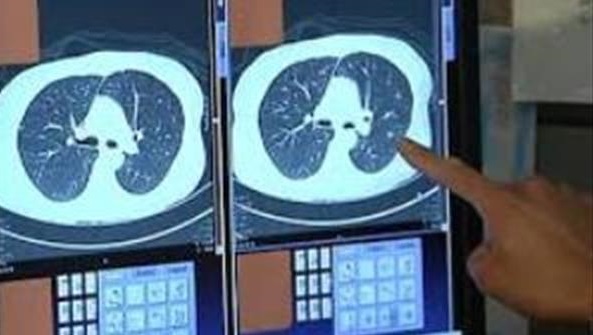

خودش رفت پیش دکتر و شرح حالم رو بدون حضور من داد و دکتر هم برام سی تی اسکن نوشت. دستور دکتر رو داد بهم و گفت:" بلند شو بیا اینجا ! این نوار زردو می بینی؟ همینو برو میرسی به سی تی اسکن."

چند دقیقه ای صبر کردم و جواب سی تی اسکن آمد . دکتر که خودش هم انگار مریض یا بی حال بود ، در حالیکه دستش رو روی سرش گرفته بود، یه نگاهی به صفحه ی مانیتورش انداخت و بعد از بالا و پایین کردن تصویر گفت: "منفیه ، مشکلی نداری برو. "